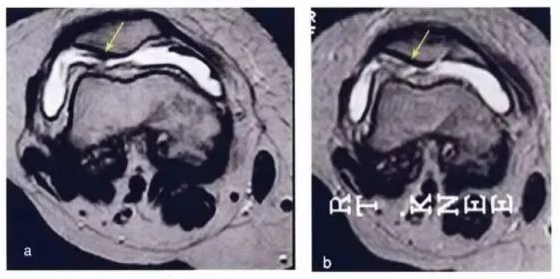

研究结果:关节内注射骨髓间充质干细胞6个月后,疼痛、功能状态和步行距离均提高。6名治疗组中3名患者在治疗前后的MRI比较可以看出,该治疗对于改善软骨厚度,修复组织延伸超过软骨下骨,以及减少软骨下骨的水肿是非常显著的

下图a示意治疗前软骨,b为治疗后6个月软骨,箭头所示为软骨修复位置。